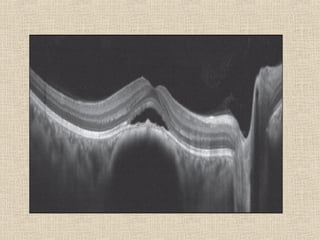

ERM – CME – CNM – ME – CSME – POST-UVEITIS – POST

INJECTIONS – MAC HOLES – PSEUDO MAC HOLES

CONCENTRATION AND QUANTITY

WAIT ENOUGH TIME OTHERWISE WAIST ALL THE TIME

EXAMPLE : MAC EDEMA DUE TO DIABETIC RETINOPATHY